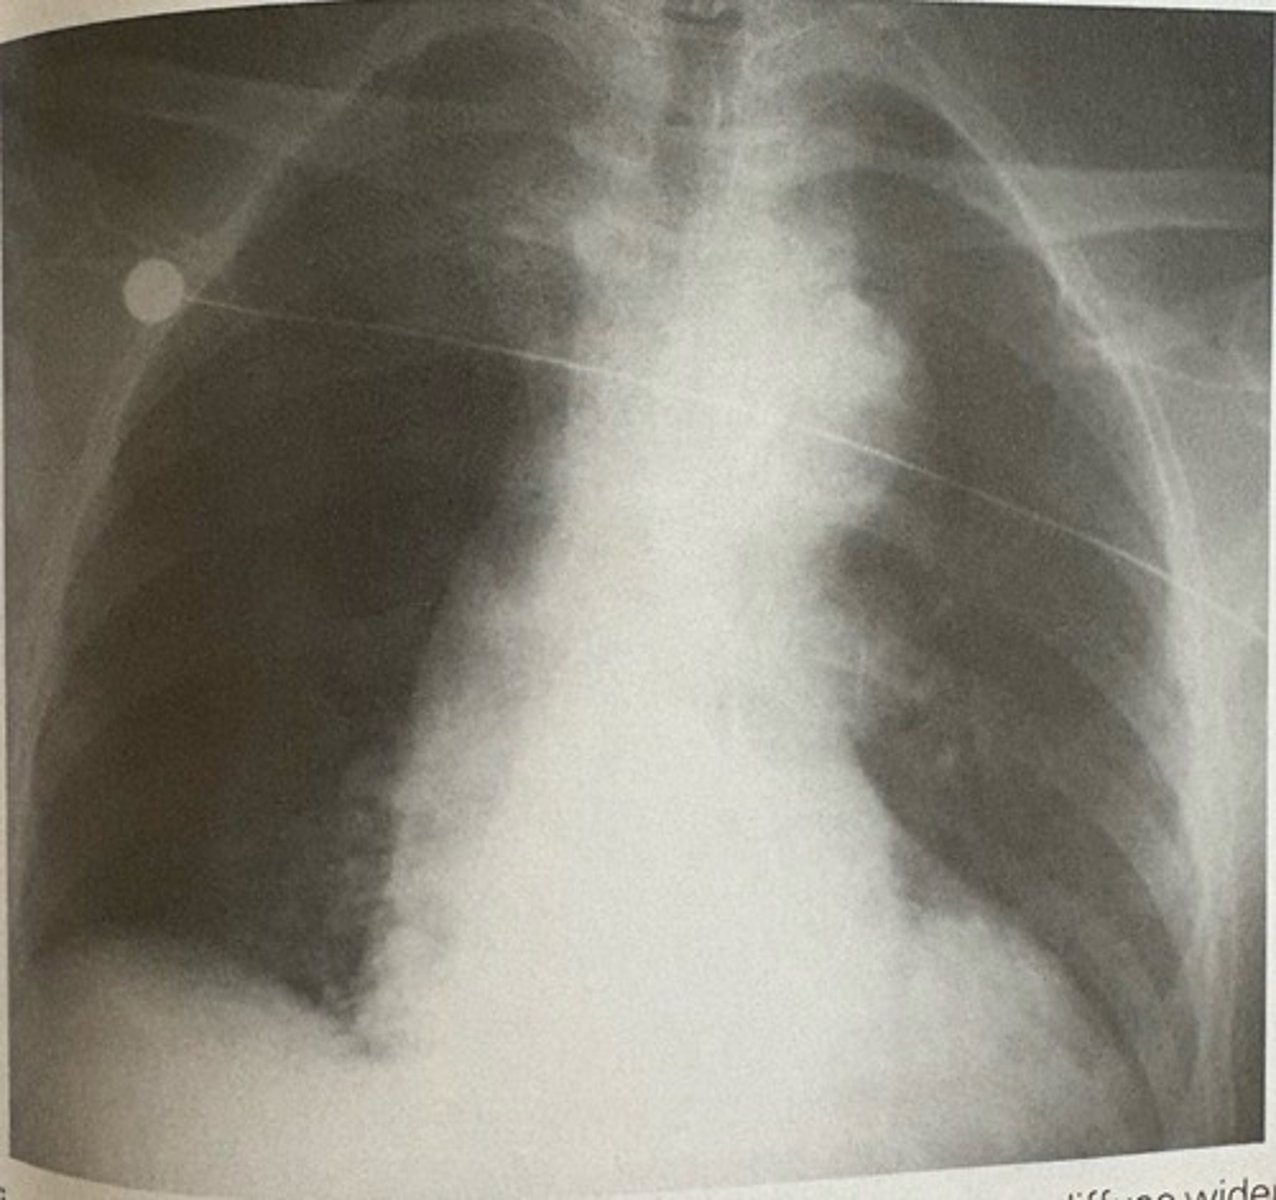

aortic dissection

what pathology is present?